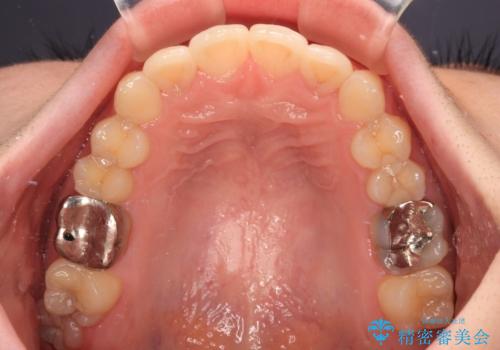

- 上下歯列全体のデコボコを気にして来院された患者様です。

主に下顎歯列全体の後方移動とIPR(歯と歯の間を削る)によってデコボコが解消するように設計し、インビザラインにより治療を行うこととしました。

1年半程度で終了するのではないかと予想しましたが、途中1年以上の来院がなく、トータルで3年の時間がかかってしまいました。

前歯のデコボコはより改善することが望ましい状態でしたが、患者様の希望により終了することとなりました。